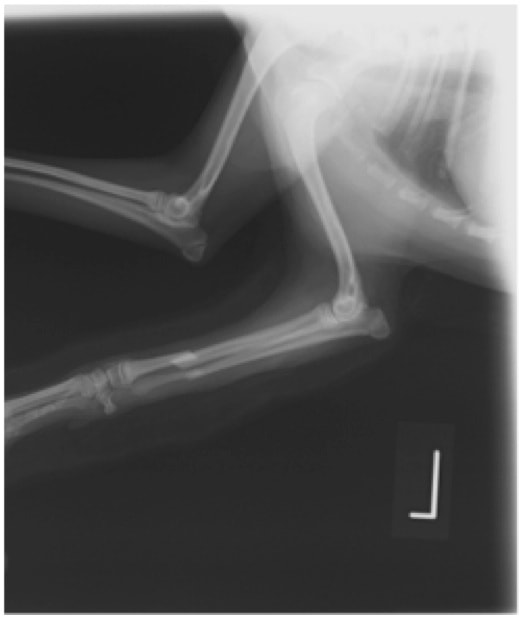

ペルシャ猫 11ヶ月齢 雄

他院にて左大腿骨遠位の成長板骨折(salter-harrisⅠ型)が認められており、治療相談を目的として来院。当院にて、キルシュナーワイヤーを用いたピンニングにより骨折部位の整復を行いました。術後の経過は良好で、現在も経過観察中です。

術前レントゲン

術後レントゲン